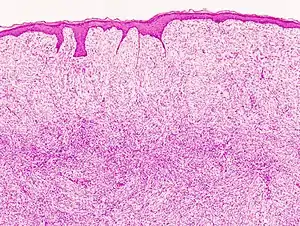

Histopathological image of dermatofibrosarcoma protuberans. Local recurrence long after the first excision. H&E stain